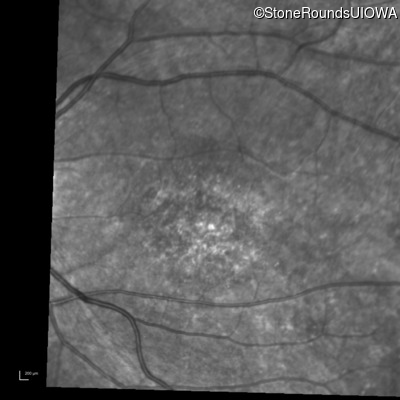

Infrared Fundus Photograph - Right - 10/160 -1 sc

Exemplar